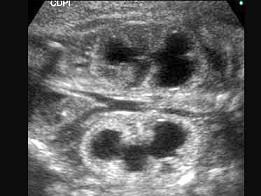

图为孕34周的胎儿声像表现。根据图像特点,最可能的诊断为 ?(?)A.多囊肾B.肾积水C.肾囊肿D.肾肿瘤E.以上都不是

问题 图为孕34周的胎儿声像表现。根据图像特点,最可能的诊断为 ?(?)

选项 A.多囊肾 B.肾积水 C.肾囊肿 D.肾肿瘤 E.以上都不是

答案 B